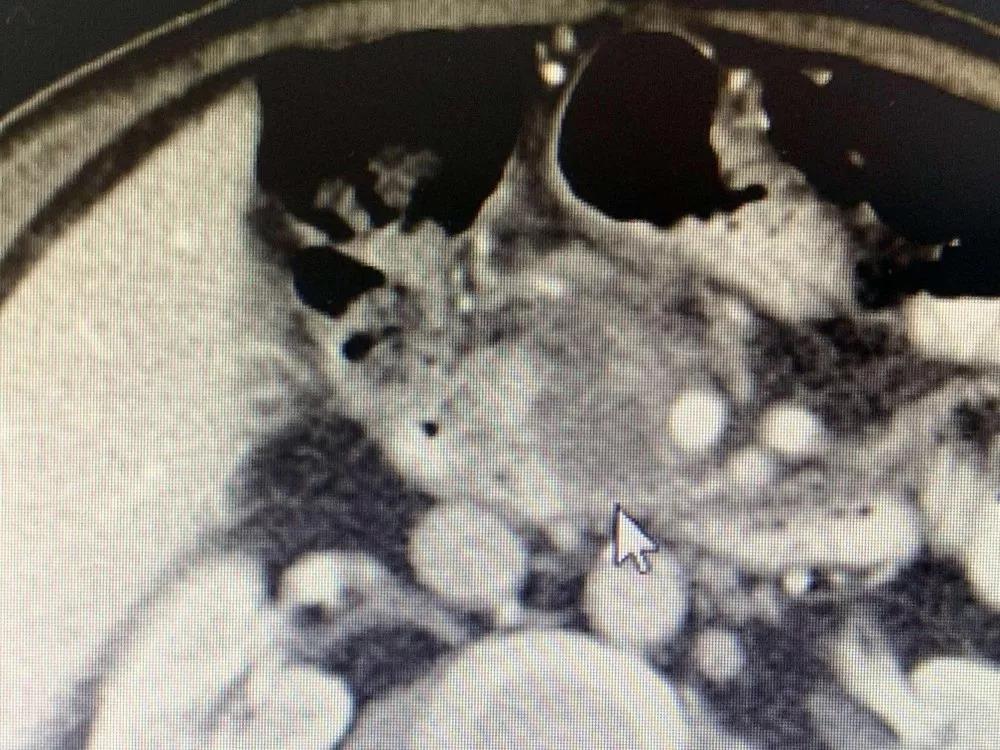

Для дальнейшего лечения как можно скорее его сын привез его в Онкологическую больницу Фуда 31 августа. После обследования ему был поставлен диагноз несоциализированная аденокарцинома III стадии в поджелудочной железе и диабет II типа с множественными узлами в печени, легких и щитовидной железе. После обсуждения с доктором Ню Личжи и медицинской командой он и его семья согласились провести катетеризацию в подключичной вене 6 сентября и на сдедующий день необратимую электропорацию при опухоли поджелудочной железы. После интенсивной терапии его состояние улучшалось с каждым днем.

Во время утреннего обхода доктор Ню и доктор Ли пришли в его палату. В то время он сидел в постели со скрещенными ногами и разговаривал со своей семьей. Когда он увидел приходящих врачей, он почувствовал себя счастливым. Доктор Ли сказал: «Через неделю после операции отчет КТ Ратана показал полный некроз опухоли, и онкомаркер СА199 вернулся к норме».